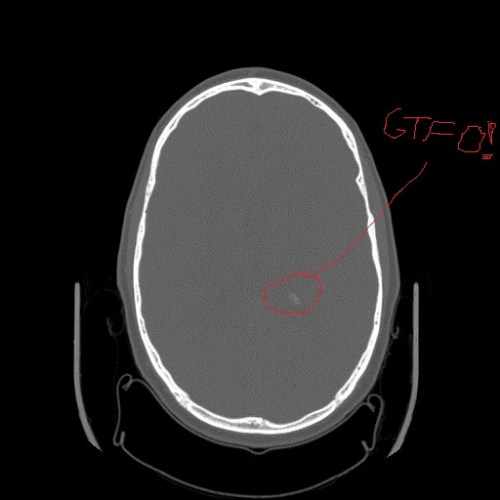

Calcification in ?ventricle? of my cerebrum.

Calcification in parietal lobe of my cerebrum, from axial CT scan slice. But no bleeding (zone of altered density/contrast).